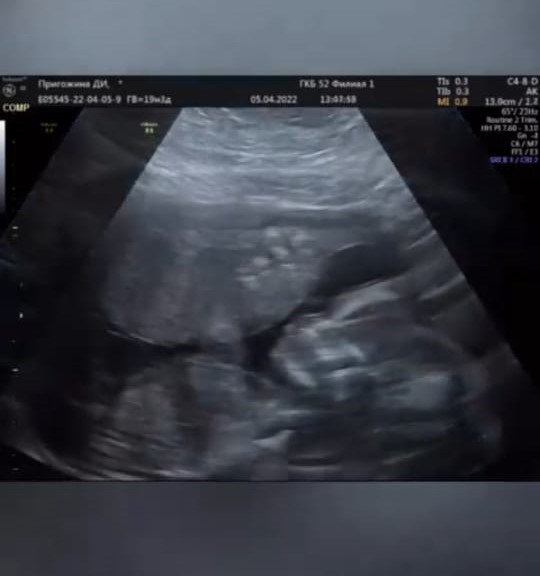

Пригожина счастлива планировать с ним жизнь и, конечно же, мечтала о совместном ребенке. Так, она с радостью объявила об этом в социальных сетях: «Очень волнительно. Признаюсь честно, у меня лучшая аудитория! И каждого, с кем я общаюсь, люблю и уважаю. Не могу не поделиться такой чудесной радостью».

Даная рассказала подробнее о беременности «СтарХиту»: «Самый популярный вопрос, наверное, будет, запланированная или нет — запланированная! Нет тут такого, что «Боже, надуло». Просто была ситуация с врачами очень нелепая, говорили: «вот, вам надо готовиться года три», а получилось довольно-таки без подготовки, все хорошо прошло. Поэтому врачам верить нельзя».

Даная с трепетом относится к своему малышуПравда, о том, кого же ждет Пригожина, брюнетка не сообщила. «Пол нам уже известен. Гендер-пати не будем делать, я просто не смогла ждать. Но однозначно мы рады! Скорее хотелось поделиться с мужем и семьей», — поделилась она.